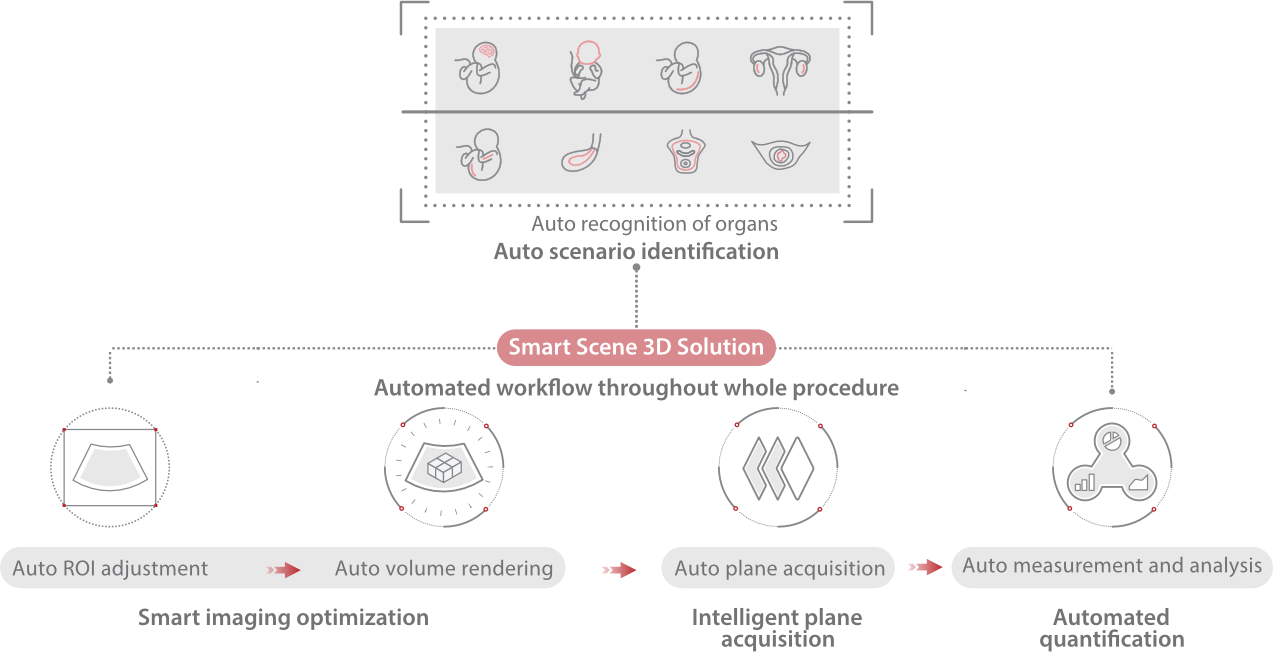

Scenario-oriented Full-stack Intelligence

Combining advanced algorithms and domain-specific knowledge, the innovative Smart Scene solution enables auto identification of tissue characteristics and provides organ-specific diagnosis with full-stack intelligence. Based on auto scenario identification, the solution not only realizes smart 2D scanning with auto settings and measurements, but also delivers 3D full-stack intelligence in every step from volume imaging optimization to the difficult 2D plane acquisition, and quantification throughout whole procedure. It helps a lot in reducing the dependency on clinical skills, while increasing diagnostic accuracy, confidence and efficiency.

Professional Ultrasound Solutions with Full-stack Intelligence

- Protecting the new lives with fertility and obstetrics solutions

- Caring for women's health with gynecology and urogynecology solutions

Fertility

Obstetrics

Gynecology

Urogynecology